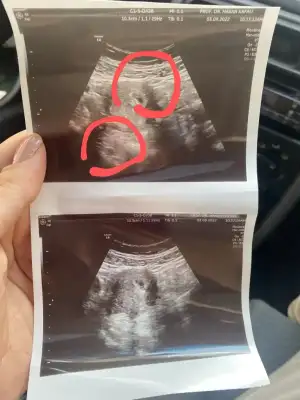

Ha kızlar bu arada benim kanamam olduğundan sonra tüp bebek doktoruma da gitmiştim kese görmeye diye ama ben zaten çoktan görmüştüm o ayrı magnezyumla omega3 te verdi progestanı da 4*200mg kullanıyorum kan sulandırıcılarla estrofemı kestiler belki bi faydası olur diye yazayım dedim